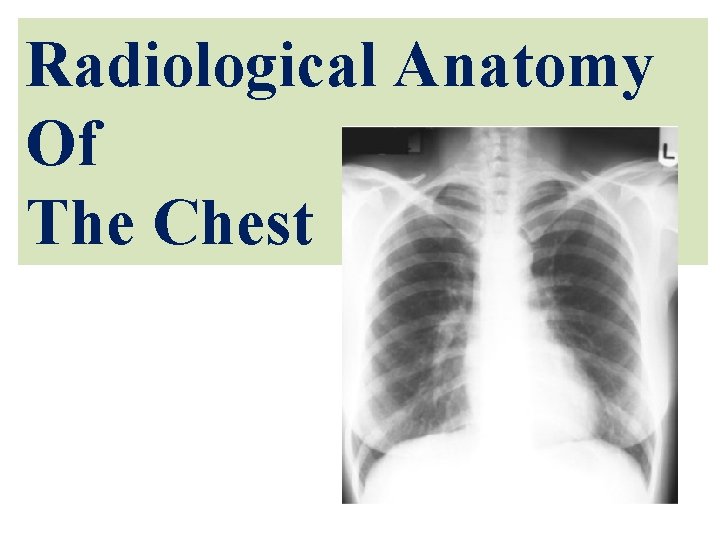

Radiological Anatomy Of The Chest

Objectives By the end of the lecture you should be able to: 1 - Identify the bones of the thoracic cage. 2 - Identify superficial soft tissues. 3 - Identify the trachea and lunge fields. 4 - Describe the mediastinum and the cardiac shadows. 5 - Describe brief knowledge about Bronchography. 6 - Describe brief knowledge about Coronary Angiography